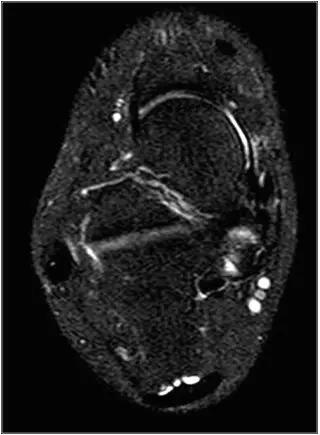

男,11岁,自述后踝下方疼痛,活动时为甚,并有一突起。

- MRI 检查示距后三角骨及周围软组织有水肿信号,距后三角骨和距骨之间正常的低信号纤维连接中断,出现液性信号。

3、MR表现:

- 三角籽骨或距骨后三角结构模糊和变形,T1WI信号降低, T2WI信号升高,

- 周围脂肪水肿,

- 踇趾长屈肌腱信号升高,见鞘膜积液,

- 胫骨后下跟骨上缘骨结构形态变化和信号异常,

- 三角籽骨和距骨退行性囊变。